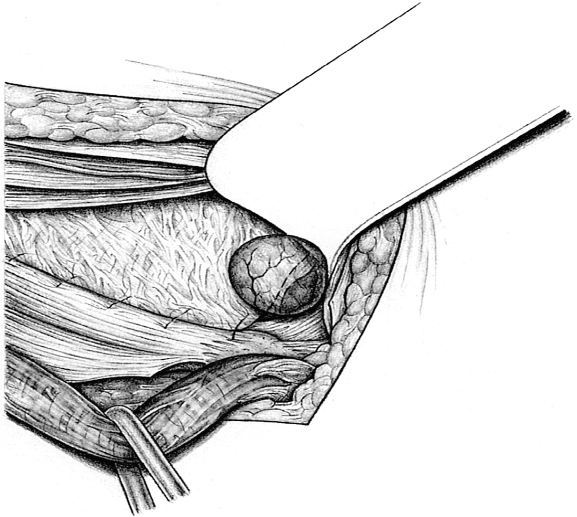

Sutured repair, e.g., by the Shouldice method (see section

2.2.2.4), can then be carried out, especially in younger patients. Unlike in men, the deep inguinal ring is closed completely. The proximal stump of the round ligament can be included in the lateral part of the Shouldice suture (

Fig. 3.2).